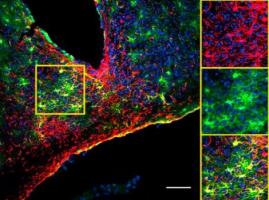

TRAUMA CÉRÉBRAL : Les astrocytes, une source naturelle de cellules souches réparatrices

PLASTICITÉ CÉRÉBRALE : Le rôle décisif des astrocytes dans le développement cognitif

DÉPRESSION : La perte d’astrocytes en cause ?

Actualité publiée le 05/03/2020De la SÉNESCENCE à la NEURODÉGÉNÉRESCENCE : Le rôle clé des astrocytes

Actualité publiée le 08/11/2019MÉMOIRE à LONG TERME : Sans astrocytes, point de consolidation

ALZHEIMER : Les astrocytes à la rescousse

PLASTICITÉ CÉRÉBRALE : La nestine, une protéine clé de la neurogenèse

HORLOGE BIOLOGIQUE : Les astrocytes, ces étoiles gardiennes du temps